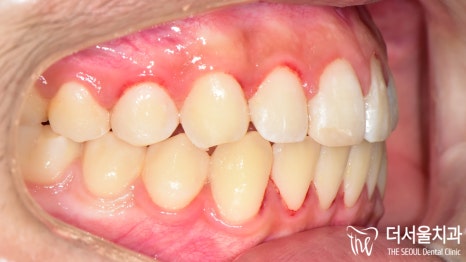

『결과』

전과는 달리 벌어졌던 이 사이도

긴밀하게 붙어 있는 것이 확인되었으며

툭 튀어나와 있던 돌출입도 개선이 되었습니다.

인비절라인 을 사용한 덕인지

이갈이 가 심한데도 불구하고

구강 내 상처나 치아 마모 등이 나타나지 않았네요.